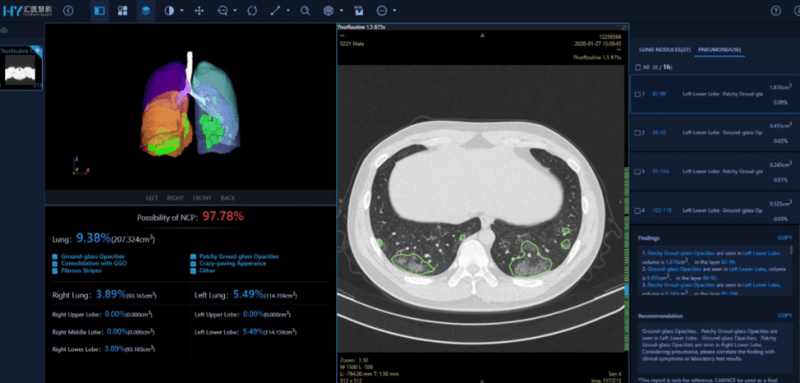

- Enhanced Diagnostic Accuracy: AI in Medical Equipment has demonstrated remarkable performance in various diagnostic tasks. For instance, an AI system achieved 94% accuracy in detecting lung nodules from medical images, significantly outperforming human radiologists who scored 65% in the same task (Scispot.com, May 31, 2025). Similarly, AI-based diagnosis has reached 90% sensitivity in breast cancer detection, compared to 78% for radiologists (Scispot.com, May 31, 2025). In emergency medicine, AI-based imaging systems have shown 85-90% accuracy in disease detection from X-rays and CT scans (PMC, Apr 1, 2025).

- Improved Image Quality and Efficiency: AI can improve the quality of images from scans, potentially reducing the need for rescans or allowing for lower radiation doses. It can also significantly reduce scan times and automate parts of the image analysis process.

- Early Disease Detection: AI’s ability to identify minute changes can lead to earlier detection of diseases like cancer or diabetic retinopathy, improving prognosis and treatment options. For example, AI tools can rule out heart attacks twice as fast as human assessment with 99.6% accuracy (Dialog Health, Dec 19, 2024).